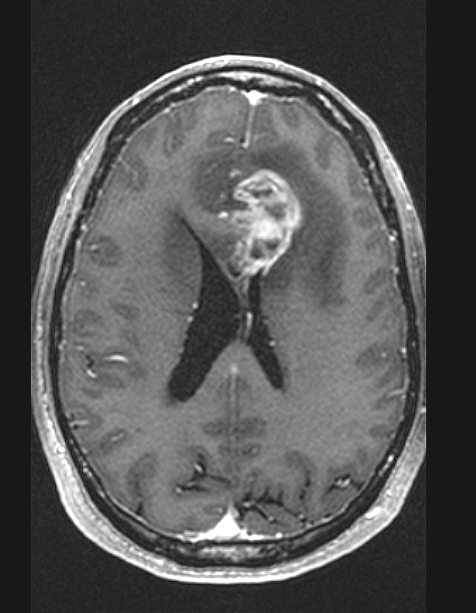

Radiology description

- MRI: T2 / fluid attenuated inversion recovery (FLAIR) bright infiltrative lesion(s) with postcontrast T1 showing irregular peripheral rim enhancement with central necrosis

- May cross the corpus callosum

- May be multifocal

- Lack of contrast enhancement may be observed in molecularly defined glioblastoma

- Certain subtypes (i.e., gliosarcoma, epithelioid, giant cell) may appear well circumscribed (Neurosurg Rev 2021;44:3335, Eur Radiol 2019;29:429, Surg Pathol Clin 2020;13:249)